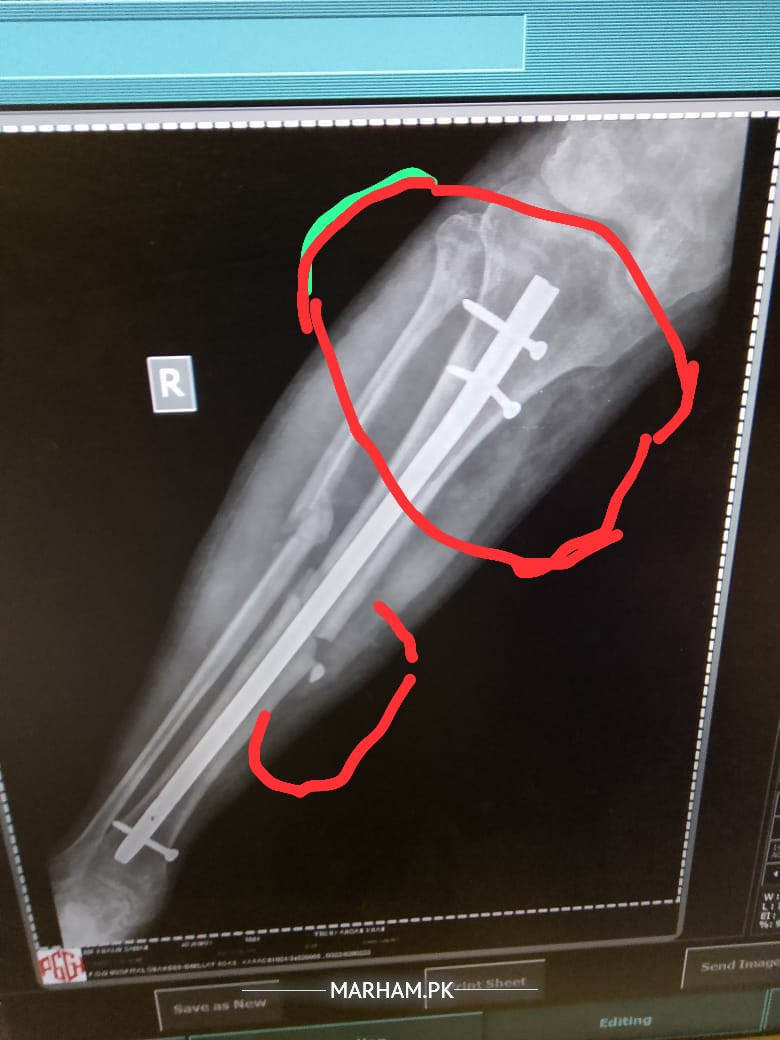

sir mane 5 month pehle opretion keya tha leg ka Lekin mere leg Mai abhi bhi pain ho Raha hai or baghir sahare k nai chal sakta sir plz check my report k Kya reason hai

seems like a case of delayed union. take vit d and calcium supplements and visit orthopaedic nearby. hopefully it will improve.

sir plz reply me k Kya Mai phir opretion karon? q k es Mai haddi ka ik piece hai jes se leg Mai soojan hothi hai or ik keel morh geya hai.plz reply me

Aap ki haddi poori tara se juri nai ay abhi jis ki waja se dard huta ay aapko koi peep waghera aati hai??

sir ye haddi ka Kya karon Jo ik chota sa peace hai